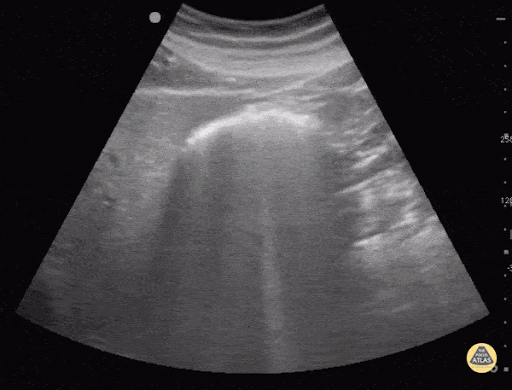

1) Use a curvilinear transducer for subxiphoid visualization by placing the probe in the epigastrium and orienting the probe toward the left shoulder to visualize the stomach. [8] (See Figure 3 and Video 2) This test is considered positive if the gastric tube is directly visualized in longitudinal and angled scans of the epigastrium. [8] If the NGT cannot be visualized, an air-water mixture consisting of 10cc of air and 40cc of normal saline can be injected through the NGT under US visualization looking for dynamic fogging in the stomach at the tip of the NGT. [8] (See Figure 4 and Video 1) No adverse events have been reported using this method, however caution should be used to avoid injection of normal saline into the tracheobronchial tree.

Figure 3. Image of the NGT in the gastric fundus in sagittal scan (left). [7] A mixture of 40 ml normal saline with 10 ml air injected into the tube to visualize the hyperechogenic "fog" exiting at the tip of the tube (white arrows, left). [4]